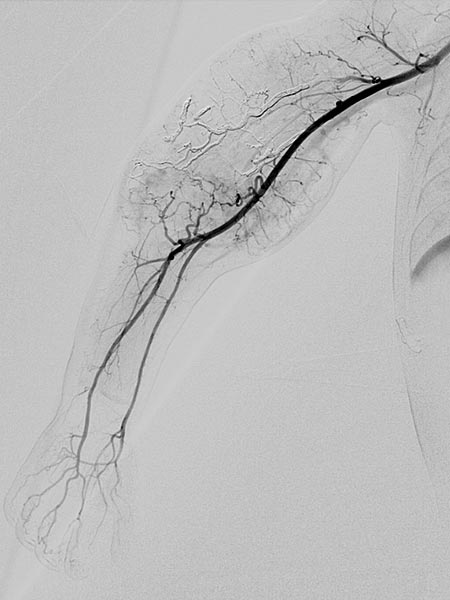

Digitale Subtraktionsangiographie links über die Arteria brachialis und rechts über den Mikrokatheter, welcher in der hypertrophierten Feederarterie am rechten Oberarm platziert wurde.

Digitale Subtraktionsangiographie nach Beginn der Embolisation mit Ethylen-Vinyl-Alkohol-Kopolymer über einen Mikrokatheter mit ablösbarer Spitze. Gleichzeitig Entnahme einer Stanzbiopsie zur histologischen Untersuchung.

Digitale Subtraktionsangiographie nach Embolisation von geschätzt 70 % der arteriellen Tumorversorgung zur Verbesserung des Kasabach-Merritt-Phänomens.